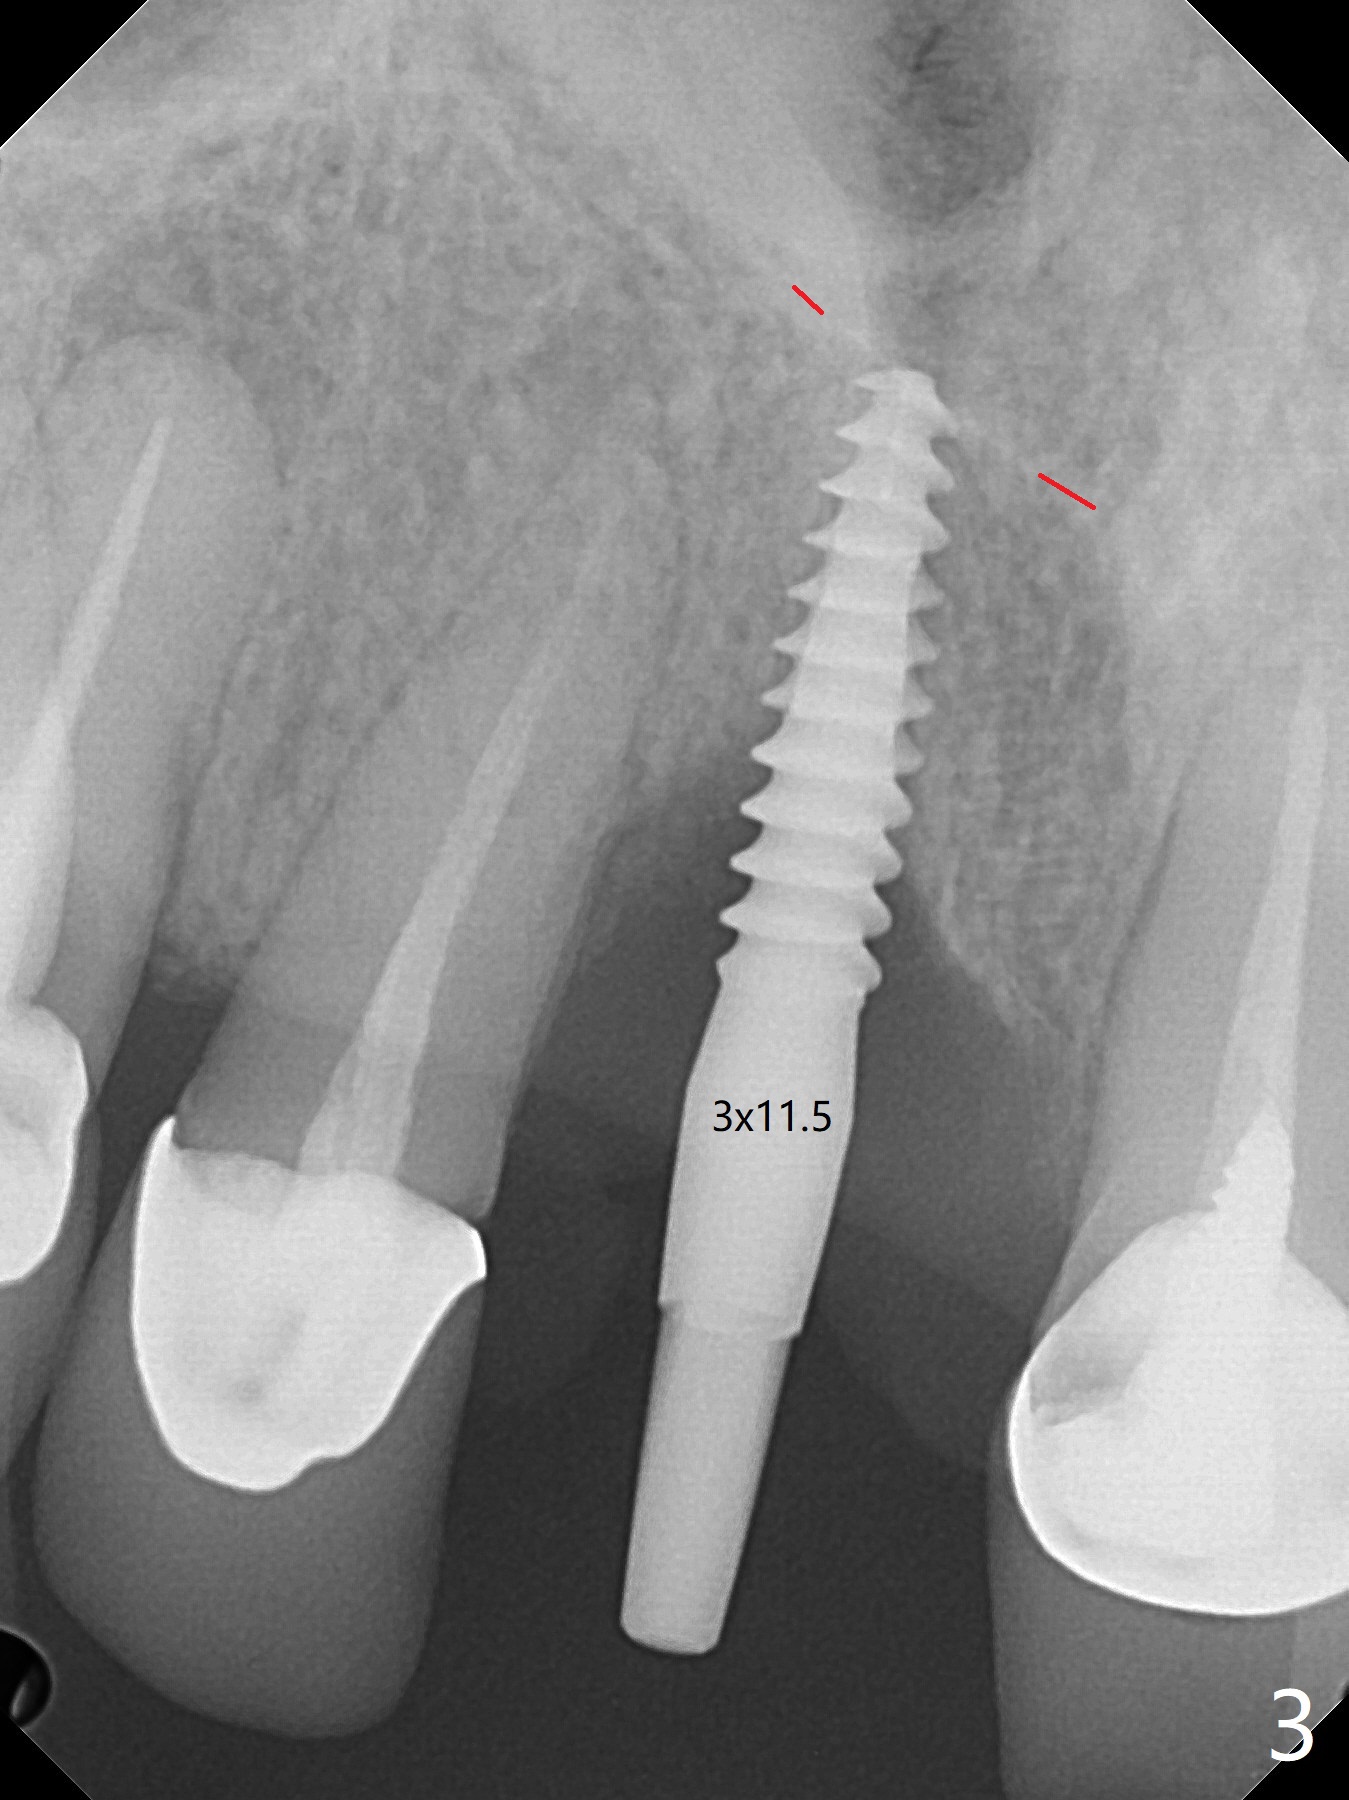

徒手初步钻洞显示方位不对(图一),重新钻洞方位尚可,好像接近鼻底(图二:红线);植入3x11.5毫米一段式植体(图三),3-5个螺纹暴露,植体似乎接近鼻底;旋转植体三趟,植体仿佛卡人鼻底,扭力大约35Ncm,植入粘性骨粉(图四,五:*)前,塞入PRF膜,紧贴颊侧粘膜,促进瘘道愈合。骨粉不仅围绕植体,而且紧贴邻牙牙根(图六(第二轮植骨:overgrafting):<)。病人术后第二周开始使用水牙线,术后三周牙龈健康多了,瘘道消失(图七)。术后六周颊侧骨壁开始塌陷(图八:>),临时牙冠颊侧颈部显得隆起(*)。调整后,牙冠外形改善(图十一至十三),取模前颊侧牙龈缘有可能下降,两个中切牙龈缘可能一致。术后3.5个月骨粉形态(图十四)与术后即刻(图六)有所不同。颊侧牙龈仍红肿轻度触痛(图十五),可能因为临时牙冠不利于局部卫生,所以决定取模制作永久性牙冠。粘固时使用临时胶水,并且涂抗菌素。另外一个可能因素是颊侧骨板薄(图十六:*),细菌感染植体螺纹,永久性牙冠粘固前,拍摄CT(放置cotton roll),必要时,植骨。永久性牙冠远中有缝隙,为了预防病人后悔,使用临时性粘固剂固定(图十七)。Return to No Caries DIO 下一个病例 一段式植体边缘制备 导板与内提升 Xin Wei, DDS, PhD, MS 1st edition 12/22/2020, last revision 06/15/2021